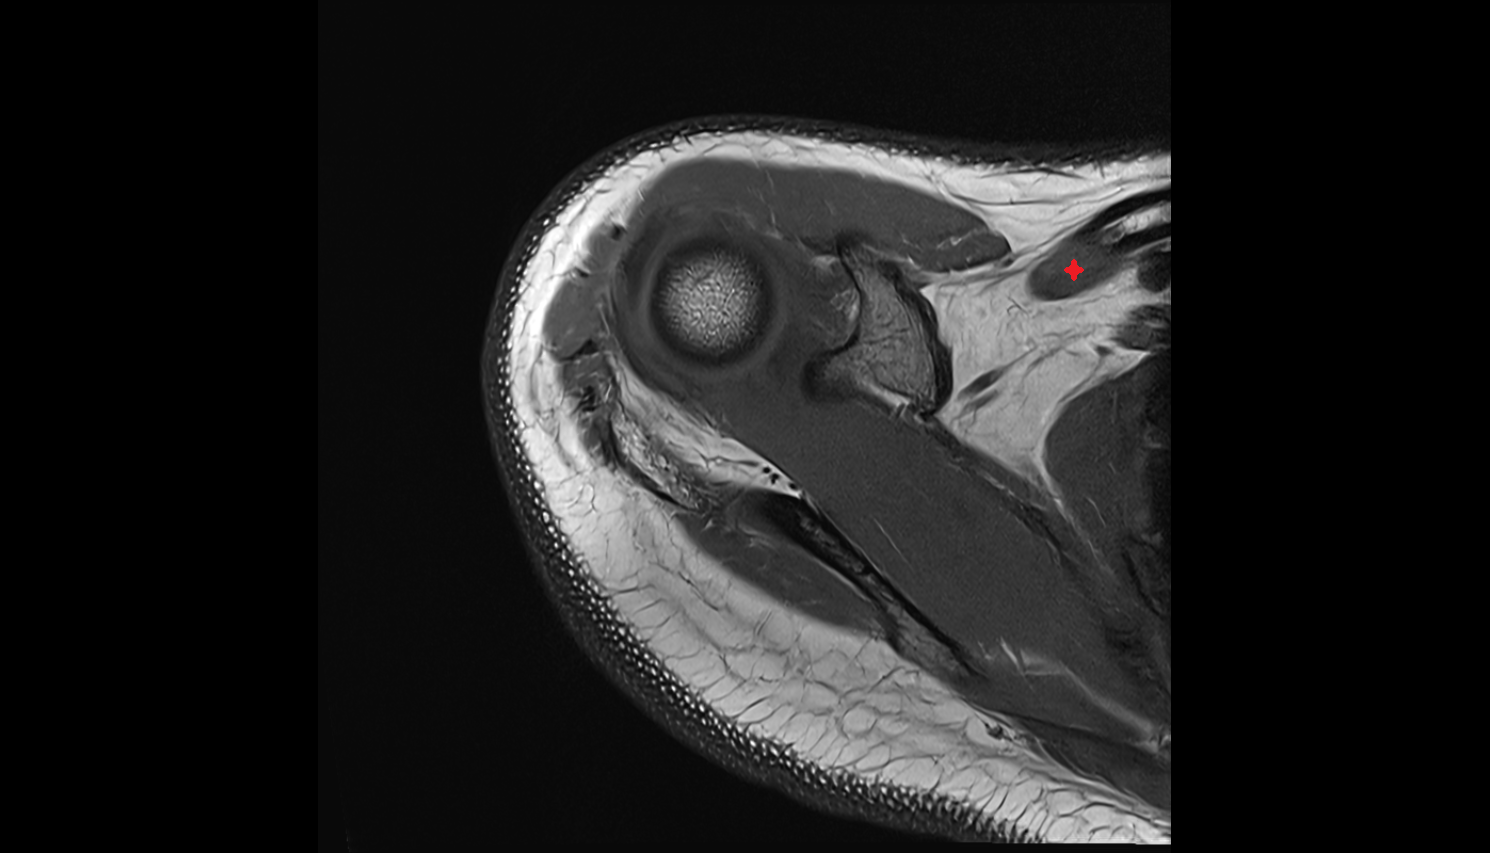

- Glenoid fossa

- Humerus

- Head of humerus

- Glenoid labrum

- Shoulder joint (glenohumeral joint)

- Articular cartilage of glenoid fossa

- Adipose tissue (Shoulder)

- Supraspinatus tendon

- Infraspinatus tendon

- Subscapularis tendon